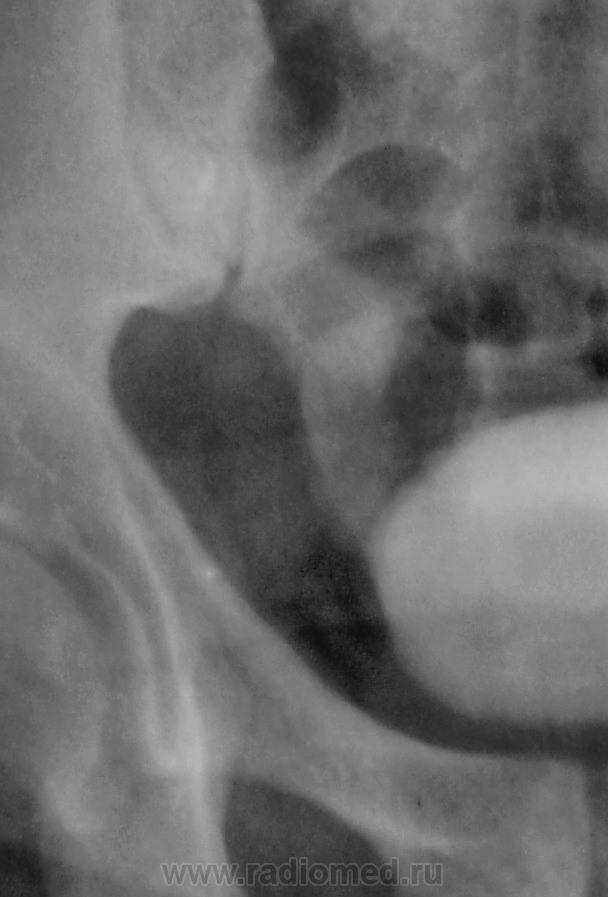

Признавайтесь, куда делась средняя треть правого мочеточника? Ее как-будто ножом отрезали под линейку, а ниже-сплошное безобразие! "ЧТО" может как обезобразить орган-банальная МКБ с частичной обтурацией просвета или опухоль? А в пузыре тоже камни?

Фи, доктор, это не латынь? Хотя можно выразиться и покрепче. Но в/в не дала ответов-где и что это?

А деформация мочевого пузыря никого не смущает?

Отчего же не смущает?))) смущает...она и есть первопричиной образования ТАКОГО камня в мочеточнике, теперь об этом можно сказать с уверенностью, ее генез - выраженое увеличение размеров простаты.

Мне кажется, что тень в проекции н/3 правого мочеточника не меняет своей интенсивности на ОМПС и экскреторных урограммах. Отсроченный снимок просится и рентгенография малого таза в косых проекциях. Возможно, это НЕЧТО сдавливает н/3 правого мочеточника извне.

С простатой при отсутствии УЗИ достаточно пальцевого осмотра хирургом до экскреторного исследования. Если простата не увеличена пальпаторно, то получив такую картинку мочевого пузыря на первых минутах после введения контраста, я бы сделал косые снимки мочевого пузыря (заодно и тень в н/3 правого мочеточника покрутить).